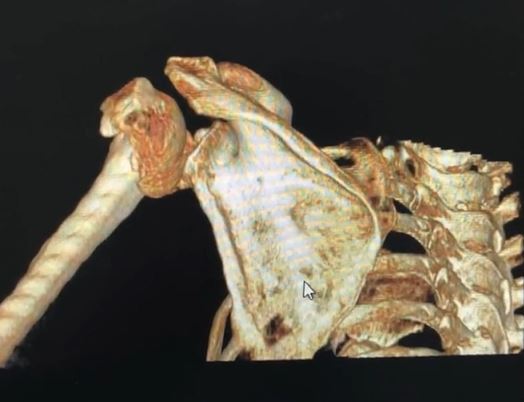

▼(圖/翻攝自 梨視頻)

浙江醫院副院長宋柏杉:「醫學上來說 叫肱骨近端骨折,還是粉碎性的比較嚴重的,她這個是雙側同時有骨折,而且輕微的力量,就導致她骨折了,所以說明她的骨頭非常脆弱。」

張姓婦人今年54歲 年紀不算大,怎麼這樣弱不經風?原來她長期服用類風濕關節炎的藥物,導致骨質疏鬆稍微用點力氣,就會造成粉碎性骨折。